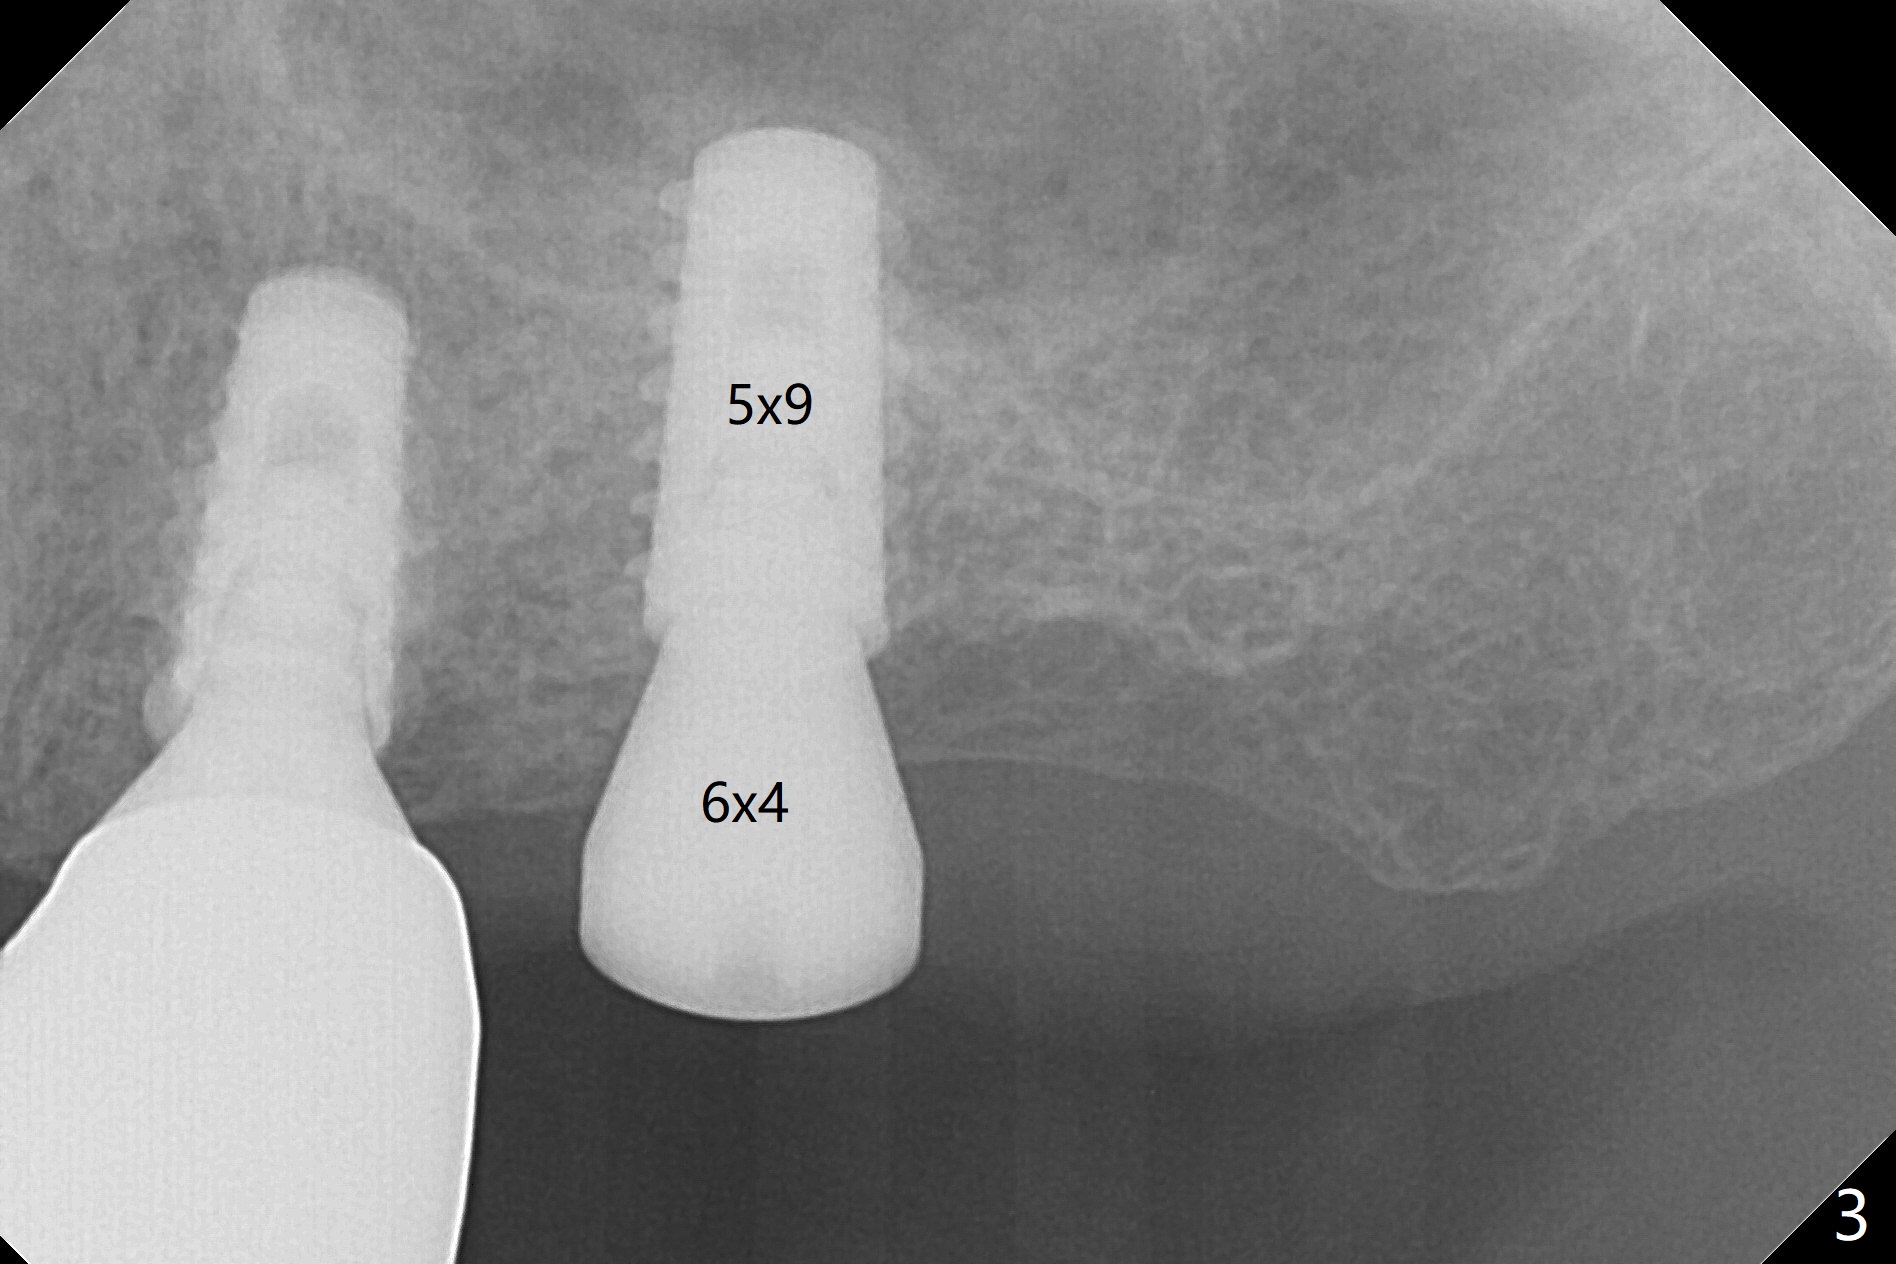

After finishing osteotomy with IS guide and Tatum Tapered tap 5x14 mm for 11 mm (gingival level) free hand, a 5x11 mm Tatum implant is placed at #18 with >15 Ncm (Fig.1). Bone harvested from the site of #18 will be used for #15 sinus lift (Fig.2 * as well as allograft). By the similar fashion, osteotomy at #15 is finished according to IS drill sequence except underdrilling (4.0x7.3 mm drill with 2 O-rings). Following use of DIO Sinus Approach Kit and placement of 2 pieces of PRF membrane and mixture of autogenous and allograft for sinus lift, a 4.5x11 mm IBS dummy implant is placed (Fig.2). With more allograft for sinus lift, a 5x9 mm implant is inserted with >35 Ncm (Fig.3). At #18 the implant 2.5 months postop (Fig.4) seems ok with removal of the cover screw and placement of a healing cuff. The implant at #15 appears osteointegrated with sinus lift 2.5 months postop (Fig.5 *). Half month later, the implant at #18 is tender associated with unipost placement. The healing abutment returns. A pair abutment (5.5x4(4) mm; 25 Ncm) is placed at #15. When the patient returns 7 months postop, BWs are taken to confirm that the abutment at #15 is fully seated, whereas that at #14 is not (Fig.6). A healing abutment is then placed at #14. Osteointegration seems to occur at #18; there is no tenderness when a 4.5x3 mm abutment is placed (Fig.7). Provisional crowns are fabricated at #15 and 18 for progressive loading. When the patient returns 14 months postop, a 5x4(4) mm hex abutment is placed at #14 with apparent gap between the implant and abutment (Fig.8 (PA) open arrow). In fact the gap seems to be absent more coronally as shown by bitewings (Fig.9,10 <). All of the 3 crowns are cemented in situ (Fig.11, 12) although the one at #14 is removed with the abutment for removal of residual cement. When the latter is re-torqued, the abutment remains completely seated (Fig.12). However, the implants at #15 and 18 appear to be placed distally with free-end guides (black lines).